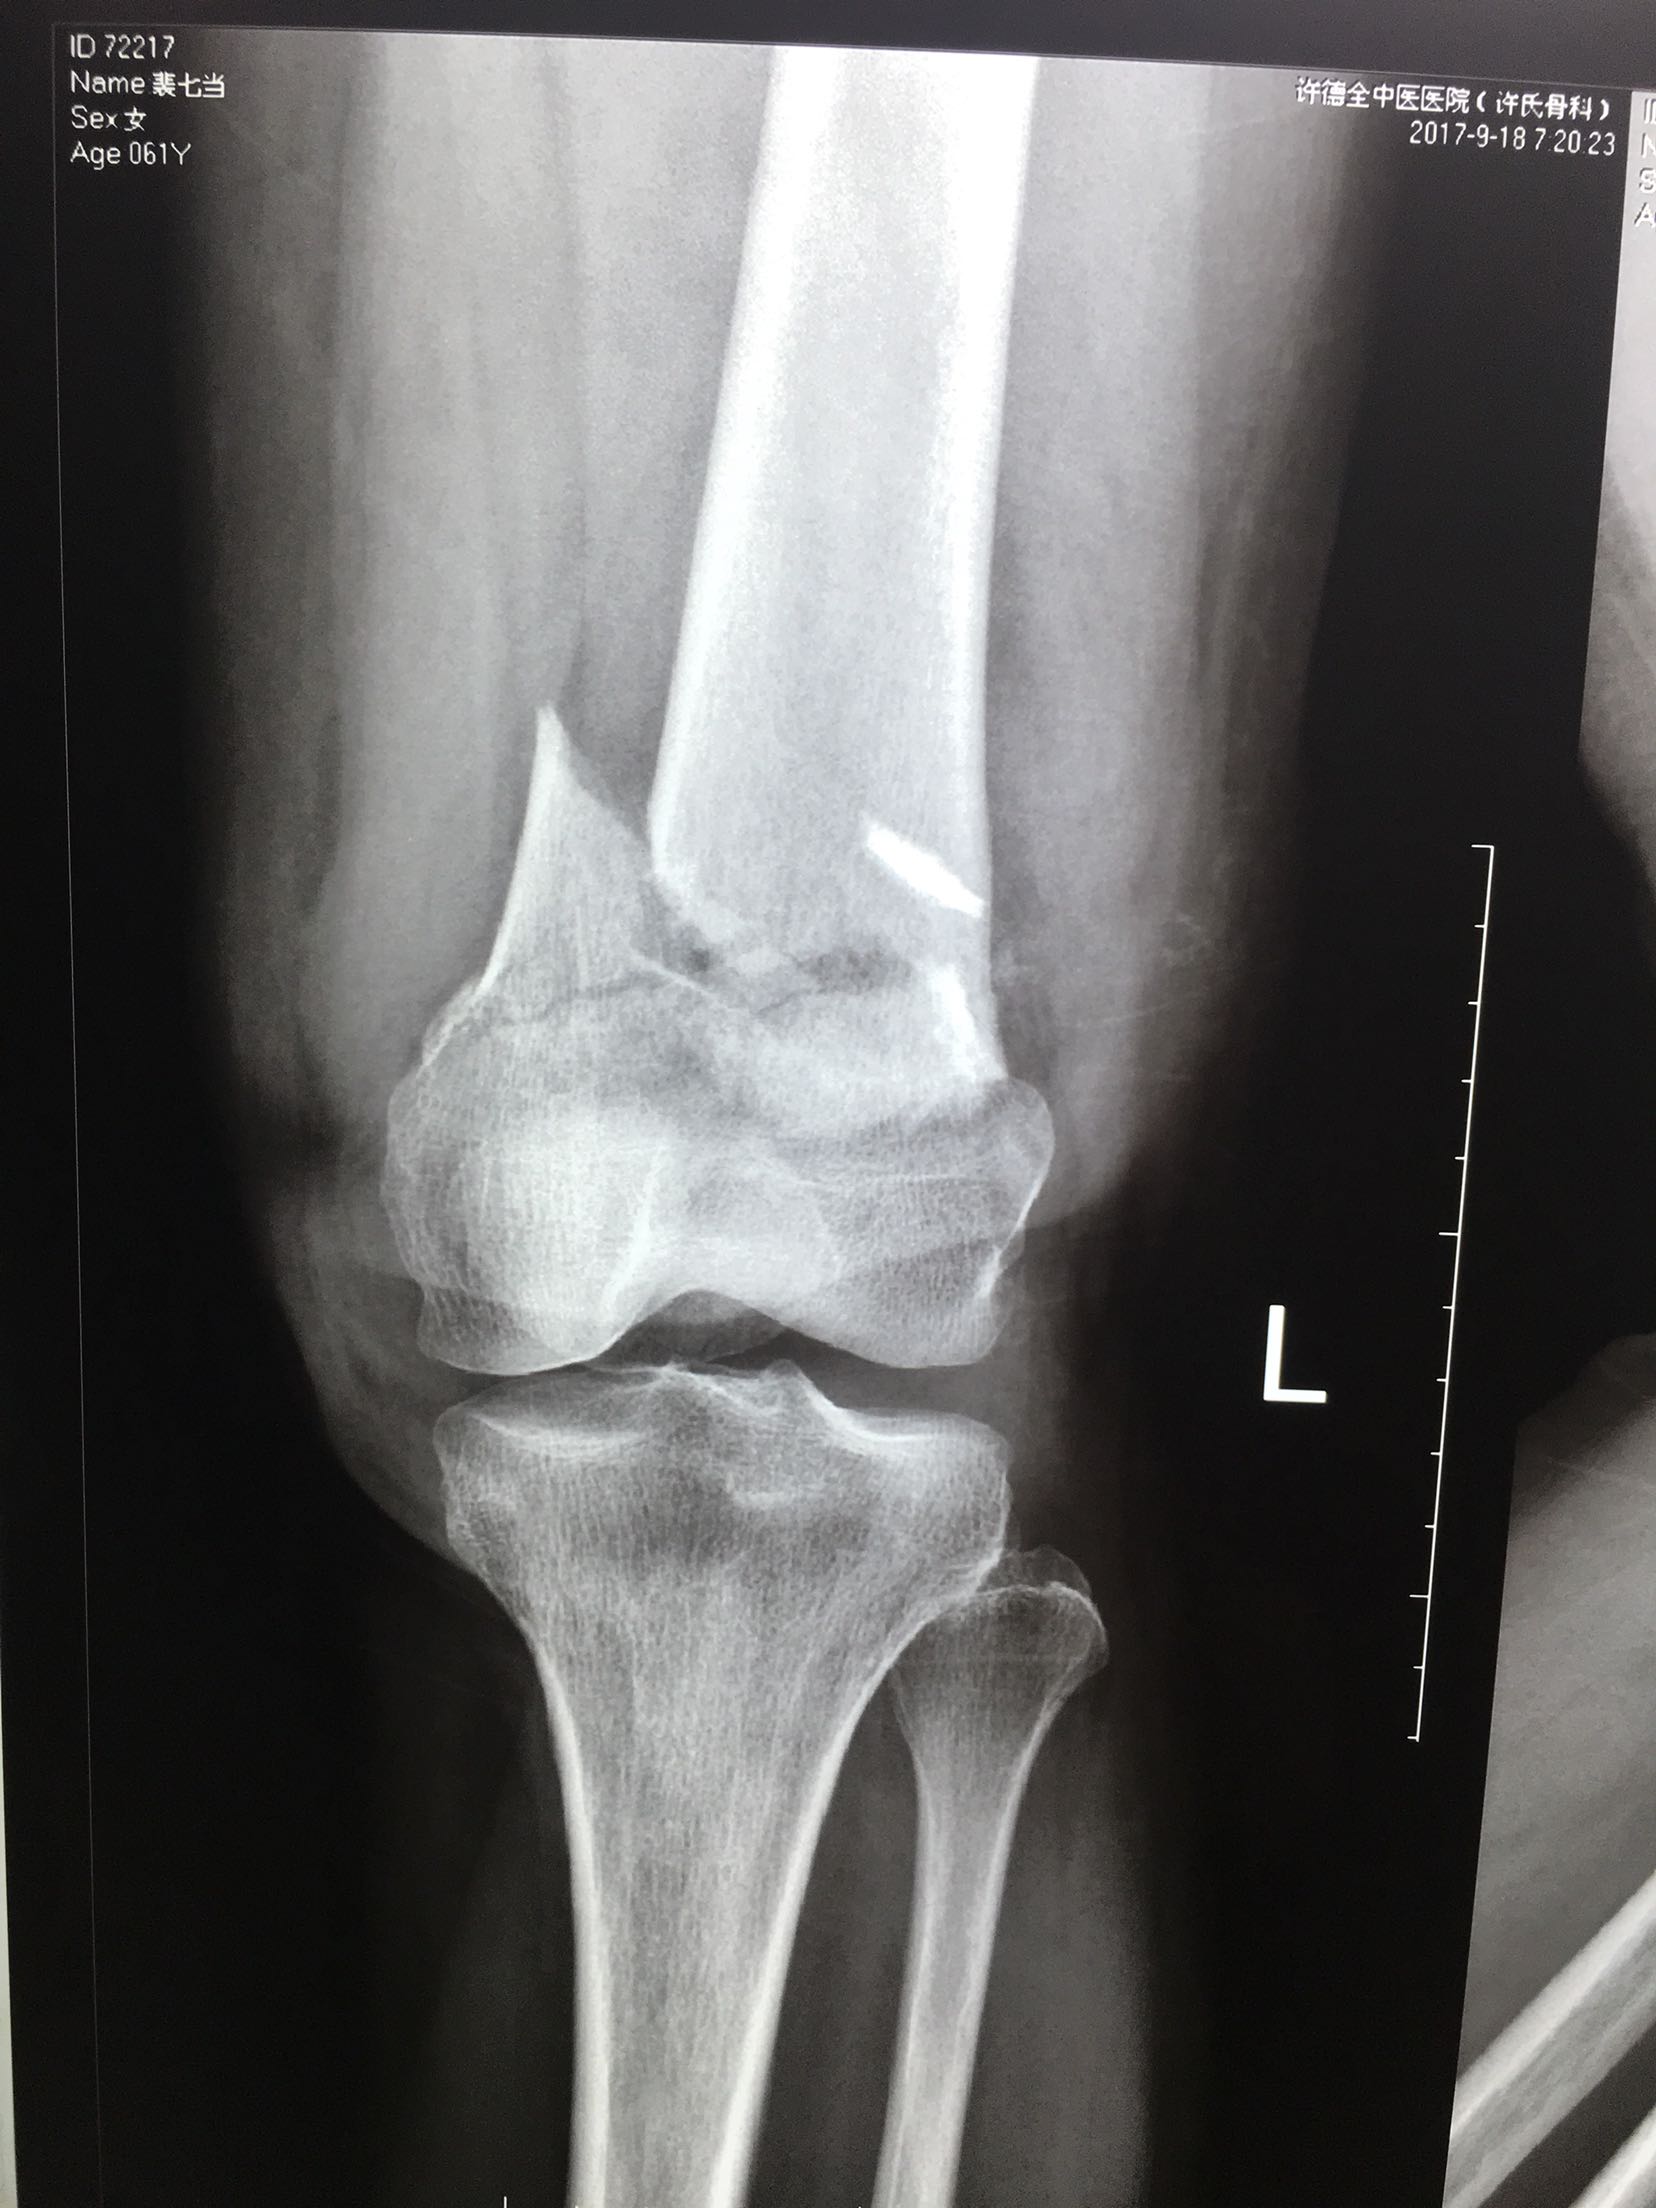

患者,女性,61岁,摔伤后左大腿疼痛,畸形,活动受限1小时。

左大腿远端局部肿胀,环形压痛,可及骨檫音,异常活动,

远端血运感觉正常。

完善检查,急诊在局麻下行胫骨结节骨牵引术。术后一周,病情平稳,在腰麻下行切复内固定术,考虑骨折粉碎,骨质疏松,拟行双钢板固定。术后抗炎,对症治疗,嘱咐一周后早期膝关节微动锻炼。